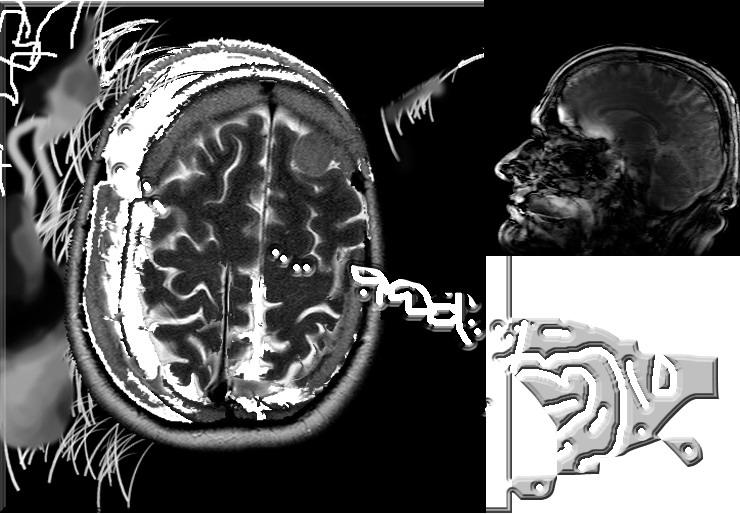

Digital 3 Grafica Digitale, Astratto informale, Computer graphics, 70x50x1cm Computer graphics life nature environment biology global warm Inserita 15 anni fa 1 Mi piace Non piace più 0 Commenti 78 Visite Condividi Facebook Twitter Google + Piace a 1 Tanya Bartolini Premium Artista - Milano Commenti 0 Inserisci commento E' necessario effettuare il login o iscriversi per inserire il commento Login